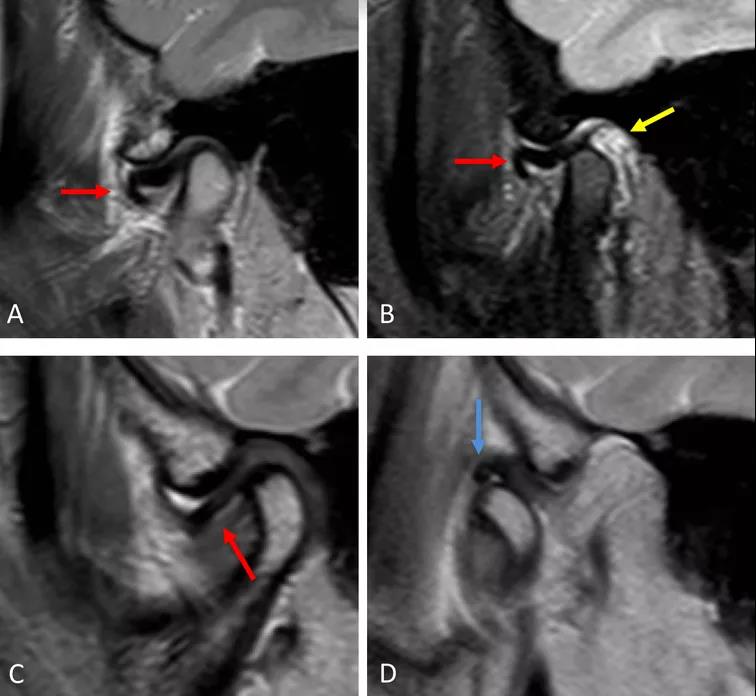

病例一:斜矢狀平面上的質(zhì)子密度加權(quán)圖像(PDWI)

A圖示:閉口位時(shí),顯示關(guān)節(jié)盤(pán)前移位明顯,雙凹形態(tài)消失。注意前帶的下移位(紅色箭頭)。

B圖示:張口位時(shí),顯示關(guān)節(jié)盤(pán)移位(紅色箭頭),關(guān)節(jié)積液(黃色箭頭)。病例2:斜矢狀平面上的質(zhì)子密度加權(quán)圖像(PDWI)